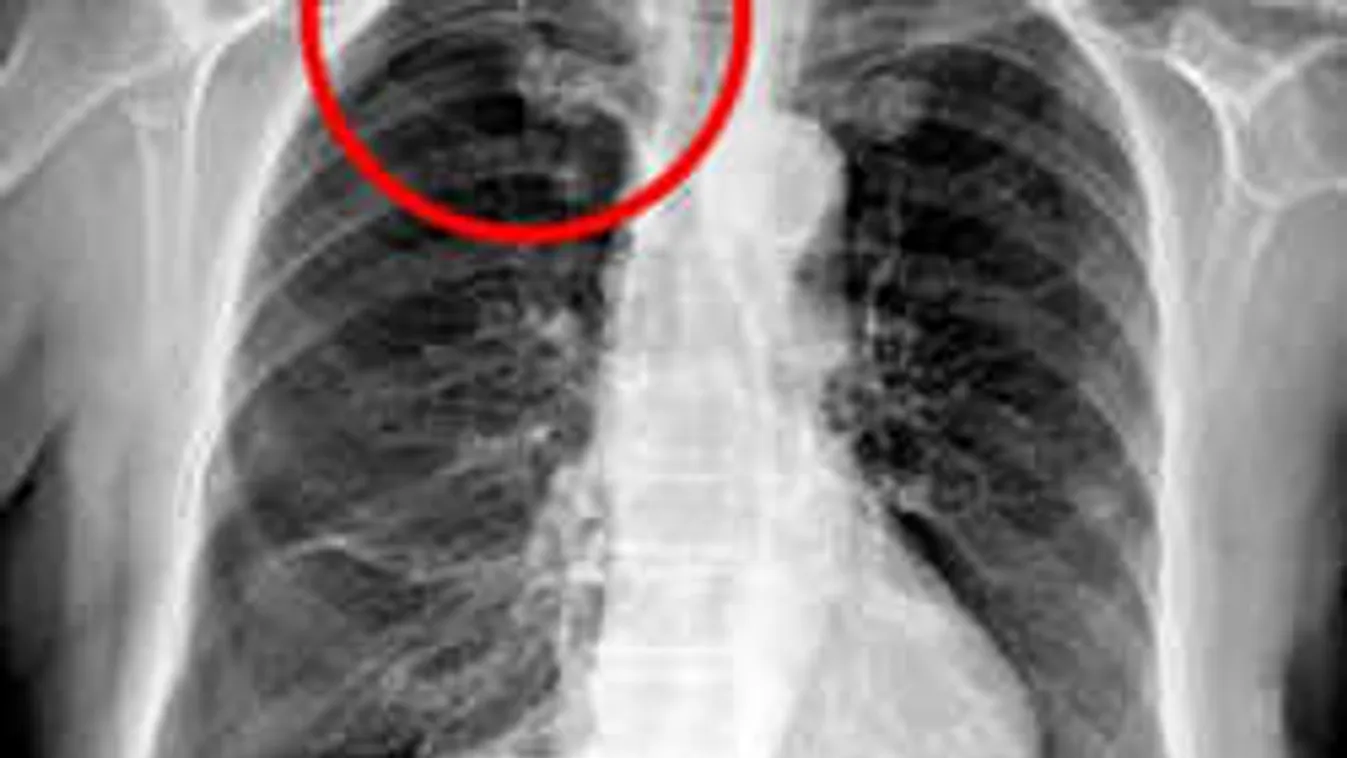

NA NE! 2019. 06. 19. Akupunktúrás kezelést kapott, horror, ami utána történt a beteggel Krónikus hátfájdalma miatt kért segítséget egy 79 éves nő. Bár ne tette volna.